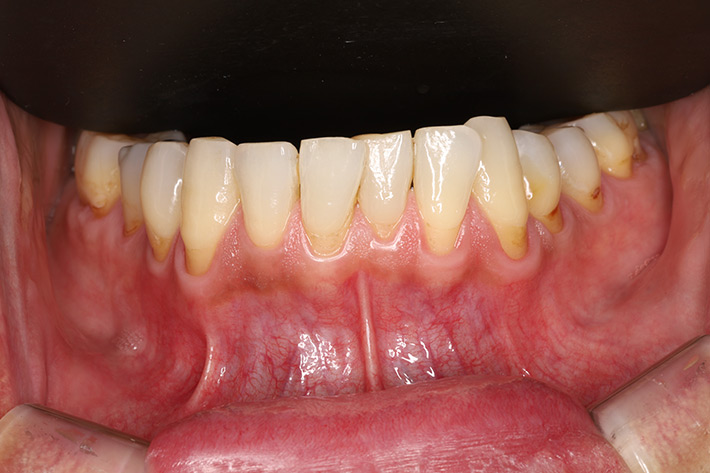

• 国分寺で唯一の「歯周病専門医」

• Periodontal Disease専門医による 重度歯周病治療、 歯周組織再生療法で 歯を残します